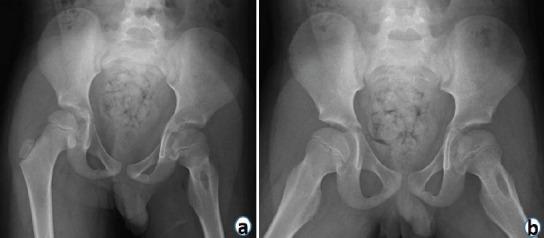

A 7-year-old male presented with complaints of hip pain and inability to bear weight. X-rays revealed Brodie's abscess in the proximal femur which was initially misdiagnosed as toxic synovitis with an incidental unicameral bone cyst (UBC).